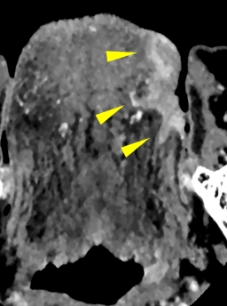

一般的に舌がんの術前の画像診断ではMRIが有用とされており、腫瘍のサイズや深さの評価が行われます。CTを使った従来の撮影方法では、歯科金属の影響でうまく腫瘍を描出することができませんでした。我々は超高精細CT(図1)を用い撮像の方法を工夫することで、舌がんをできるだけ正確に測定する試みを行っています。そうすることで非常に細かい、いわゆるキレイな画像を作成することができ、腫瘍の境界を鮮明に描出し、腫瘍のサイズをより正確に測定することが可能になりました(図2)